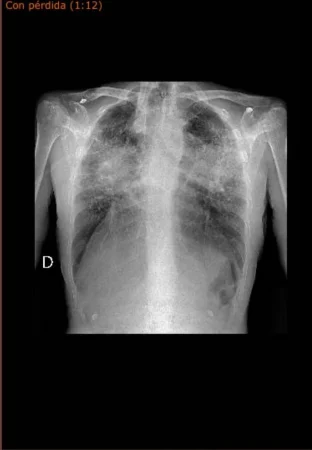

«EN EL TAC SALEN UNA GRAN CANTIDAD DE NÓDULOS MILIMÉTRICOS, Y EL MÁS GRANDE, EN MI CASO TIENE 6,5 MILÍMETROS»

José Humberto, extrabajador de Cosentino

En cuanto a los médicos, principalmente se basan en los test que al enfermo le realizan. En este sentido, en una radiografía no se nota claramente hasta que el nódulo es grande. En cambio, en un TAC salen los nódulos milimétricos y la morfología que tienen dichos nódulos. «A mí ya me habían realizado, aparte de un TAC por la mutua privada donde me habían salido nódulos, cuando paso al hospital público me realizan dos TAC más, y me salen una gran cantidad de nódulos milimétricos y el más grande que tiene 6,5 milímetros. Entonces, me diagnosticaron que tenía una silicosis crónica simple», señala José Humberto a MERCA2.